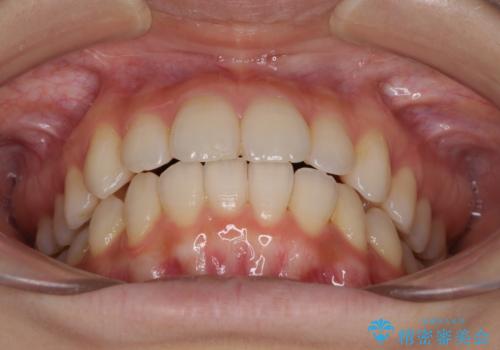

- 前歯のデコボコを気にして来院された患者様です。

叢生と捻転が随所に認められるものの、マウスピースで十分対応可能であったため、インビザラインにて矯正治療を行うこととしました。

マウスピース矯正は毎日しっかりと装着することがとても大切です。

こちらの方はしっかりと指示を守って装着してくださったため、予定通り治療を終えることができました。